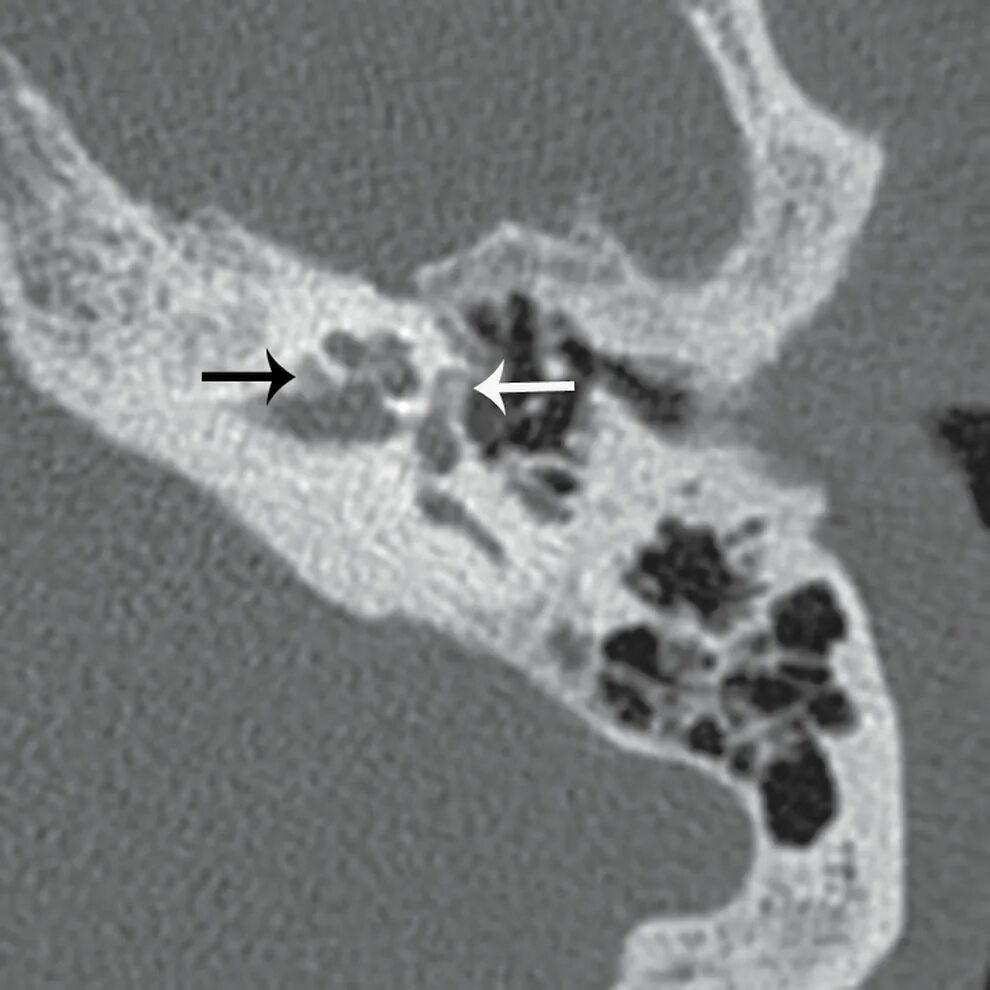

Кохлеарный отосклероз